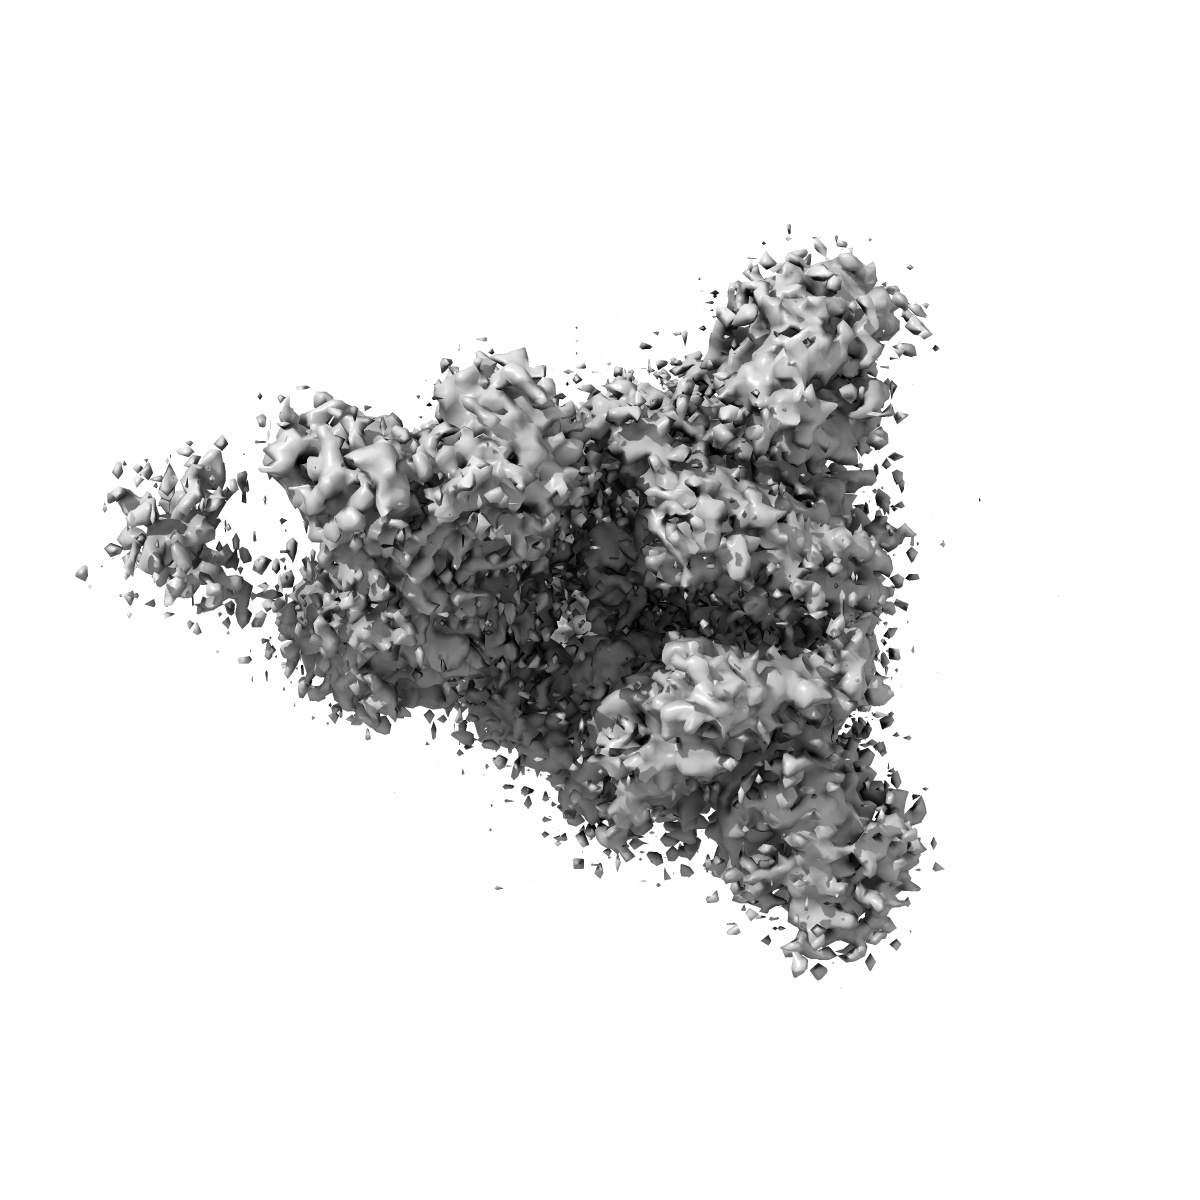

Spike_GSAS_6P and R1-32 Fab with 3to1 ratio

Single-particle4.75 Å

Sample: SARS-CoV-2 S-GSAS/6P spike trimer bound to R1-32 Fab with 3:1 ratio